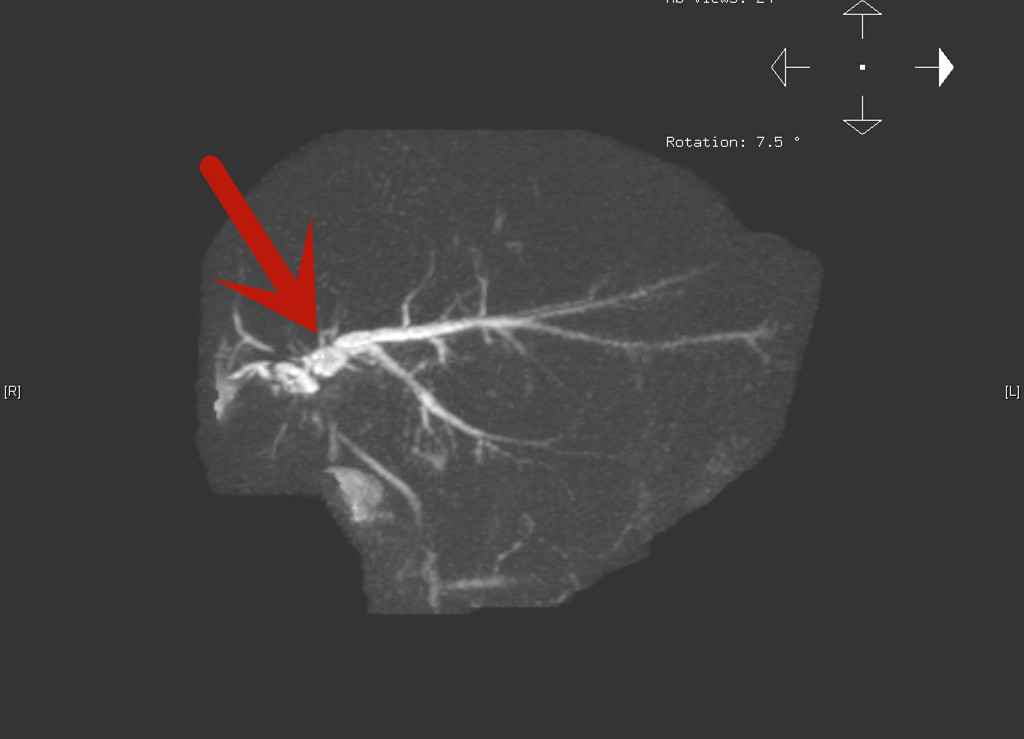

磁共振影像可见胆管堵塞位置(红色箭头处)较高

经当地主刀医师的推荐,琳琳一家来到北京清华长庚医院找到了项灿宏。评估病情后,项灿宏发现小女孩的病情比较棘手,除第一次手术造成的腹腔粘连外,“右肝切除后左肝增生、肝门区的结构发生了扭转。”项灿宏说,“而且琳琳的胆管较细,第一次胆管修补后胆管狭窄的位置较高,如何在术中准确找到左肝管并进行高质量的胆肠吻合是个巨大的挑战。”